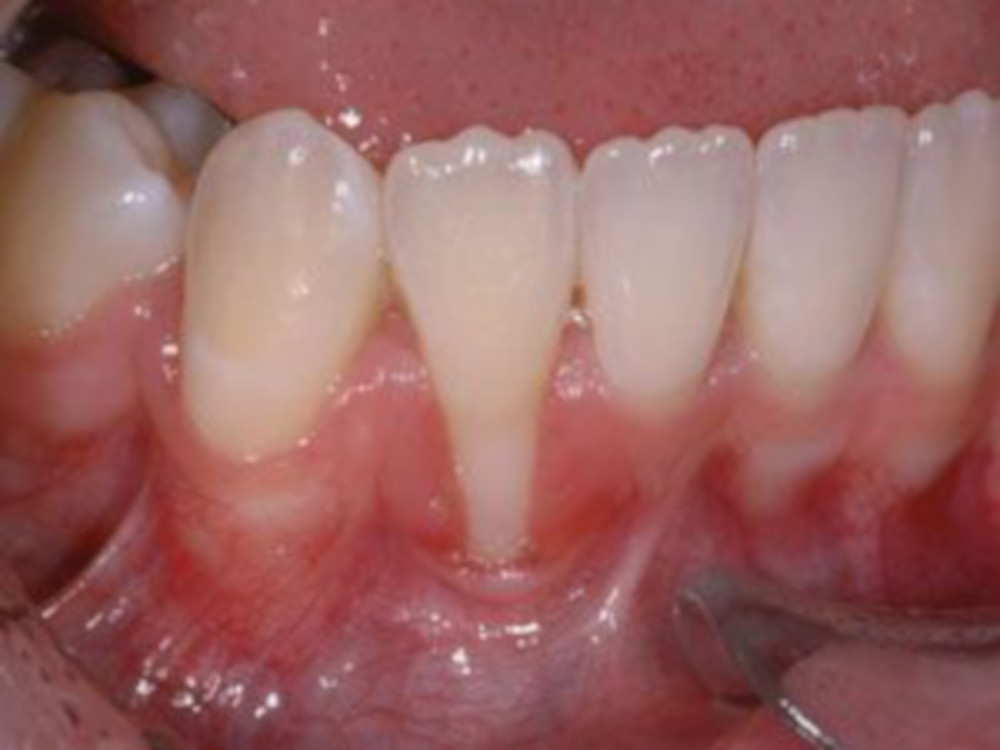

Uma das reações da gengiva é conhecida como retração gengival. Esse processo é lento e se caracteriza por uma gengiva posicionada acima da margem gengival em um ou mais dentes.

Gengiva Retraída

1) Exposição da raiz ao meio bucal. É fácil notar a coloração um tom mais escuro no seu dente quando existe uma gengiva retraída, essa cor é característica da raiz dentária. Ela não está preparada para ficar exposta em meio bucal, por isso, a agregação de placa bacteriana e o desenvolvimento de cárie pode se mais fácil que na superfície dentária;

2) Dor. A superfície da raiz gera mais sensibilidade que a superfície dentária, pois não existe uma camada de esmalte protetora sobre ela. Por isso, pacientes com gengiva retraída queixam-se muito mais de sensibilidade; e

2) Estética. Um dente com gengiva retraída possui sua estética comprometida, principalmente quando se trata de dentes anteriores.